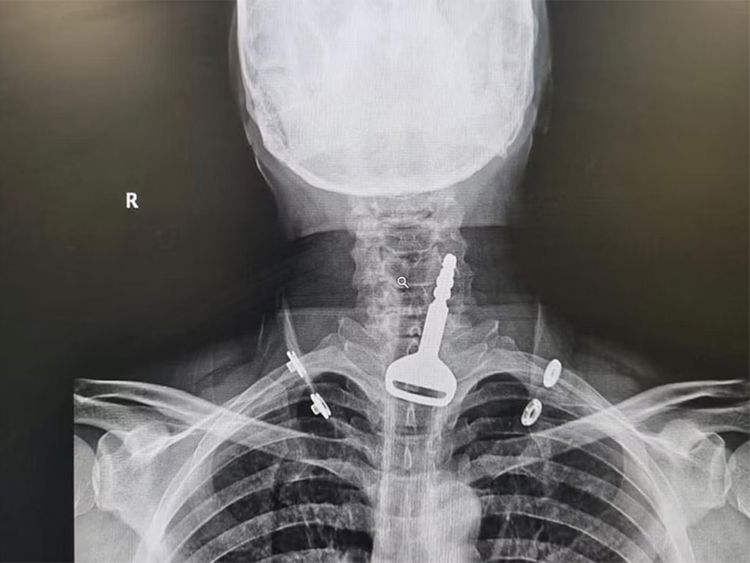

Umugabo wo muri Saudi Arabia yabazwe by’igitaraganya mu rwego rwo kumufungurira inzira z’ubuhumekero kuko yari yatangiye kubura umwuka nyuma yo kumira urufunguzo ku bw’impanuka mu gihe yarimo arukinisha.